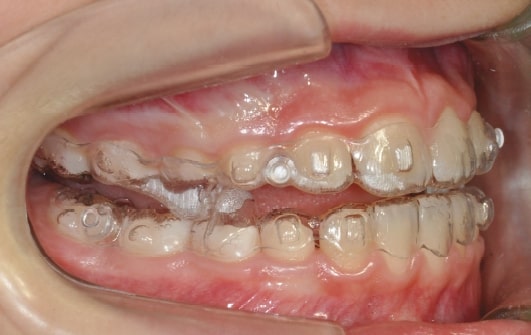

• Mandibular Advancement (A6 protocol) + angelBuon for Class 2 Elastics (Night Time)

Treatment details

AngelAligner KiD 1 (aligners changed every 10 days)

• Upper frenulum surgery

• Class 1 both sides

• Overjet/Overbite Correction

Treatment progress